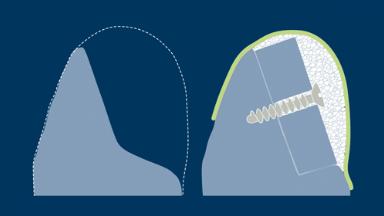

Diante do requisito de se instalar implantes na posição correta determinada pelo planejamento protético prévio geralmente significa que há falta de volume ósseo para incorporar completamente o implante. Implantes que não são completamente cobertos por osso podem apresentar risco em uma variedade de complicações, incluindo recessão de tecidos moles, inflamação e infecção devido à colonização da superfície do implante exposto à biofilmes bacterianos e até a perda do implante devido ao suporte ósseo insuficiente. Procedimentos de enxerto para aumentar o volume do osso são frequentemente necessários para garantir que os implantes estejam completamente cobertos de osso. Este módulo descreverá a composição e a natureza do osso vivo, materiais de enxertia utilizados na implantodontia, bem como diferentes modos de cicatrização de diferentes enxertos.

- descrever os principais aspectos da cicatrização do enxerto ósseo